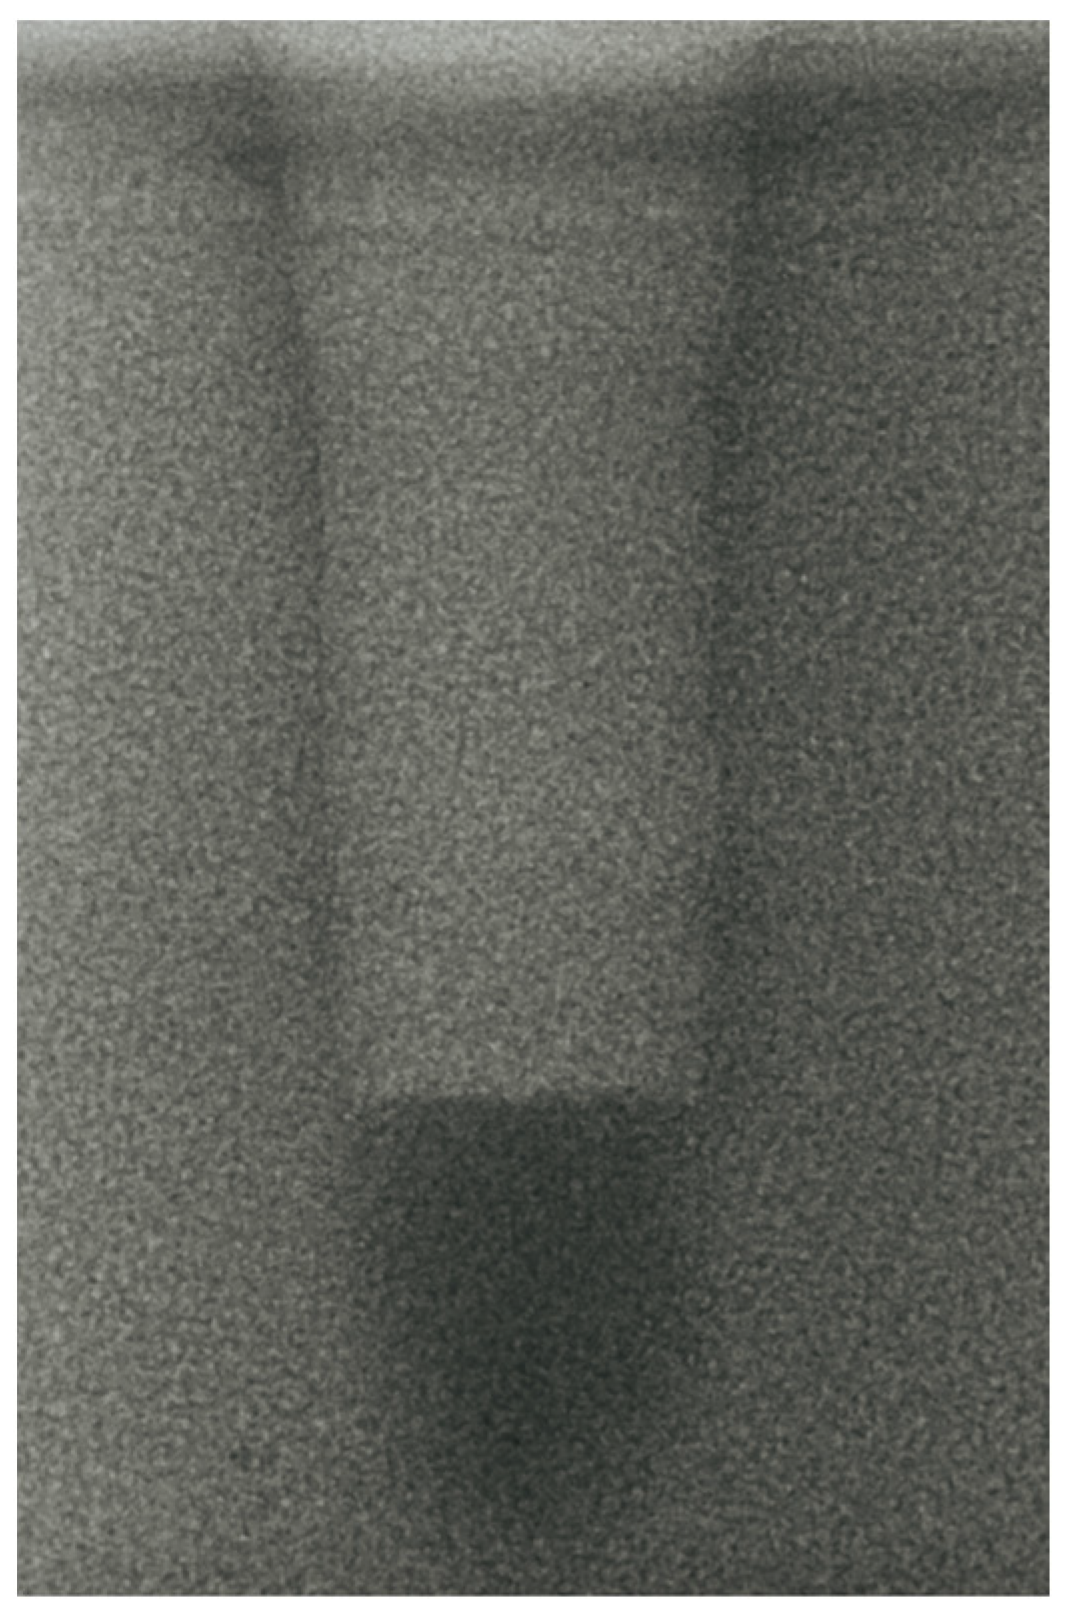

- Vertical effect of magnetic mallet: The forces produced by the MM are transmitted to the tip of the osteotome in order to achieve the plastic deformation of the bone. These forces can affect the bone in three dimensions: horizontally, vertically, and sagittally. However, the vertical effect of the MM goes beyond the area that is in direct contact with the instrument’s tip. By employing a Micro-CT scan, we accurately measured the extent of condensed bone located apically to the preparation site. The results indicate a direct correlation between the size of the condensed area and the density of the bone. Figure 3 shows an implant prepared site employing the MM technique in a bone density of 30 PCF. The length of our preparation measured 11 mm, while the condensed bone resulting from osteotomy extended 3.7 ± 0.14 mm apically to the implant site preparation. By comparing the MM with the other preparation techniques in the same bone density, we observed that, in the sites prepared using the PES approach, the vertical effect of the preparation was noticeably less than that of the MM. It extended apically to the implant site preparation at 0.36 ± 0.08 mm, as shown in Figure 4. When employing the TD technique, we noticed that the vertical effect of this preparation method was minimal compared to the MM and PES, measuring 0.15 ± 0.04 mm, as shown in Figure 5.